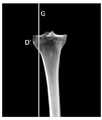

在本发明实施例中,如图3B所示,在三维图像中识别出胫骨平台上,即胫骨近端,距离外侧边缘第三预设距离处的第三关键点D之后,可以通过第三关键点D做胫骨矢状面的第一平行面G,本发明实施例对通过第三关键点确定第一平行面的实现方法不作限定。In this embodiment of the present invention, as shown in FIG. 3B , after identifying the third key point D on the tibial plateau, that is, the proximal end of the tibia, at a third preset distance from the lateral edge in the three-dimensional image, the third key Point D is the first parallel plane G of the sagittal plane of the tibia, and the embodiment of the present invention does not limit the implementation method of determining the first parallel plane through the third key point.

请参阅图7A,图7A是本发明提供的通过三维图像识别第三关键点并确定第一平行面的流程示意图,如图7A所示,在胫骨平台距离外侧边缘第三预设距离处识别第三关键点,通过第三关键点做胫骨矢状面的第一平行面至少包括:Please refer to FIG. 7A . FIG. 7A is a schematic flowchart of identifying the third key point and determining the first parallel plane through a three-dimensional image provided by the present invention. As shown in FIG. 7A , the third preset distance from the tibial plateau to the outer edge is identified Three key points, the first parallel plane of the sagittal plane of the tibia through the third key point includes at least:

701,对包含胫骨与腓骨的三维图像做胫骨的冠状面投影,得到胫骨的冠状面图像。701. Perform a coronal projection of the tibia on the three-dimensional image including the tibia and the fibula to obtain a coronal image of the tibia.

702,在所得到的胫骨的冠状面图像中,识别胫骨近端最外侧点。702. In the obtained coronal image of the tibia, identify the outermost point of the proximal tibia.

703,从所识别的最外侧点向内侧沿图像横轴在与最外侧点相距第三预设距离处识别第三关键点。703. Identify a third key point at a third preset distance from the outermost point along the horizontal axis of the image from the identified outermost point to the inner side.

704,通过第三关键点做一条平行于图像纵轴的直线,以所做的直线为第一平行面在冠状面图像中的投影,确定第一平行面。704. Draw a straight line parallel to the longitudinal axis of the image through the third key point, and use the drawn straight line as the projection of the first parallel plane on the coronal plane image to determine the first parallel plane.

在本发明实施例中,如图7B所示,可以对包含胫骨与腓骨的三维图像做胫骨的冠状面投影,得到胫骨的冠状面图像,可以以冠状面图像左上角为坐标原点,以图像横轴方向为X轴的正方向,以图像纵轴方向为Z轴的正方向,建立二维直角坐标系。然后计算冠状面图像上胫骨部分所有像素点的x坐标,并按照从小到大的顺序进行排列,将其中x坐标最小的点识别为胫骨最外侧点D’。在识别出胫骨最外侧点D’之后,将从D’点向胫骨内侧沿图像横轴移动第三预设距离处胫骨上的点识别为第三关键点D,例如第三预设距离为1cm。通过第三关键点D做一条平行于图像纵轴的直线,以这条直线作为第一平行面G在冠状面图像中的投影,来确定第一平行面G。In the embodiment of the present invention, as shown in FIG. 7B , the coronal plane projection of the tibia can be performed on the three-dimensional image including the tibia and the fibula to obtain the coronal plane image of the tibia. The axis direction is the positive direction of the X axis, and the vertical axis direction of the image is the positive direction of the Z axis to establish a two-dimensional Cartesian coordinate system. Then calculate the x-coordinates of all the pixels of the tibia on the coronal image, and arrange them in ascending order, and identify the point with the smallest x-coordinate as the outermost point D' of the tibia. After identifying the outermost point D' of the tibia, the point on the tibia where the point D' is moved to the inner side of the tibia by a third preset distance along the horizontal axis of the image is identified as the third key point D, for example, the third preset distance is 1cm . A straight line parallel to the longitudinal axis of the image is drawn through the third key point D, and the straight line is used as the projection of the first parallel plane G in the coronal plane image to determine the first parallel plane G.